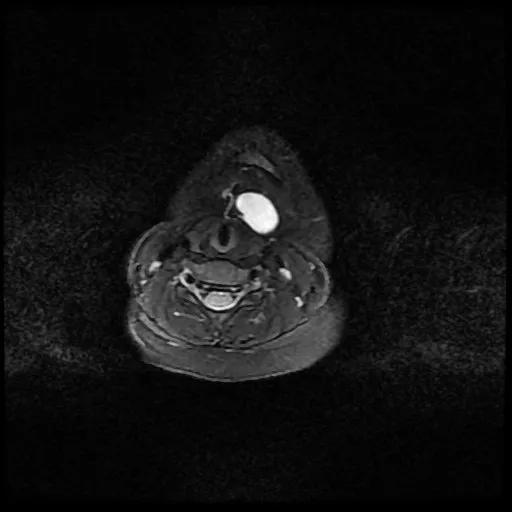

甲状舌管囊肿 MRI 水平位图像

重庆北部宽仁医院耳鼻咽喉科刘蓉蓉主任接诊后,经过高分辨率磁共振检查,再次证实了小新患甲状舌管囊肿的诊断,基本排除「异位甲状腺」等可能性。同时发现小新的囊肿与舌骨粘连紧密,有瘘管一直向上发展与舌盲孔相通,完整切除包块的难度比预想中要大。